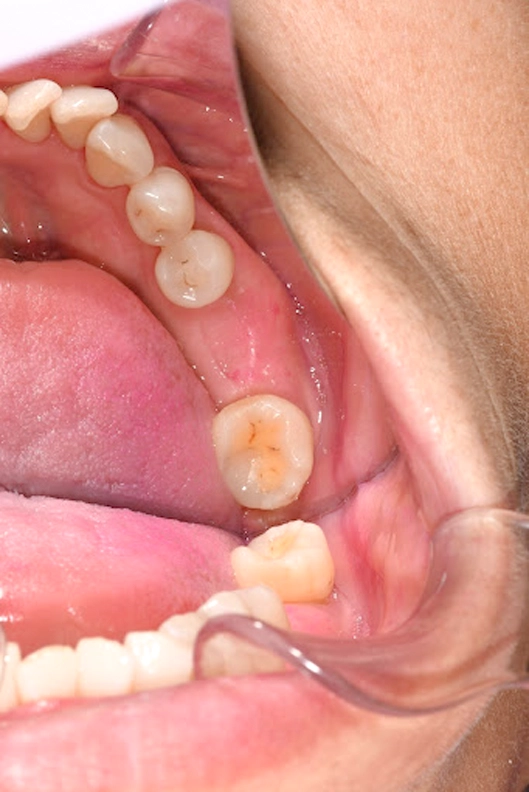

Lower (L) 1st molar:

Already restored with an implant and final crown, both functional and stable.

- Lower left first molar: The lower left first molar had already been restored with an implant and crown in an earlier stage of treatment. We included it in this case report as a reference point to show the stability and function of her implant work over time.